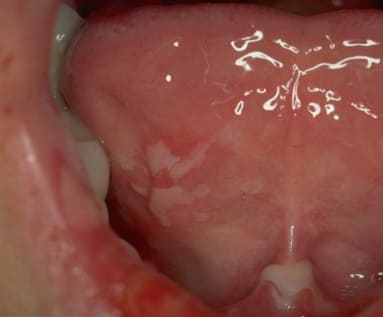

Pemphigis Vulgaris =الفقاع الشائع